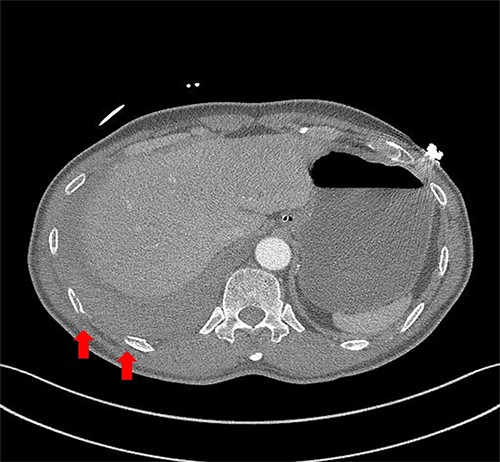

A 59-year-old man was admitted with multiple rib fractures and liver contusion due to a fall injury. He was standing on a chair for working at a farm, and it was knocked over causing him to fall and hit his flank against the corner of the chair. There was continuous pain while resting at the right flank and severe pain with pressure was noted, but no external wounds or bruises were observed. There were right 7th–11th rib fractures, scanty pneumothorax, minimal hemothorax and a 2-cm-sized liver contusion in abdomen and chest computed tomography (CT) scan (Fig. 1A, B). He was hospitalized for pain control and close observation in the general ward, and conservative management was initiated. Also, no significant changes were noted in the following daily follow-up chest radiographs. The patient suddenly complained of right-sided chest and back pain aggravation, cold sweating and fatigue 80 h after the traumatic injury. His mental status was alert, but v/s including systolic blood pressure (SBP) of 100–120 mmHg, heart rate (HR) of 40-60 beats/min and oxygen saturation of 100% during the admission changed to an SBP of 86/60 mmHg, HR of 88 beats/min and oxygen saturation of 97% when the symptoms occurred. Chest radiography was performed after the patient experienced aggravated symptoms, such as right-sided flank pain, cold sweating and fatigue. Compared to the previous scans, signs of increased opacification and peribronchial and parenchymal infiltrations were observed, which were indicative of hemothorax (Fig. 2A, B). We performed enhanced dynamic chest CT to identify any presence of active bleeding. On the chest CT scan, a large amount of hemothorax was identified in the right lung field along with multiple fractures of the right ribs. However, there were no signs of contrast leakage indicative of active bleeding (Fig. 3). Hemoglobin levels decreased from 13.1 g/dl on the day before the symptoms appeared to 11.5 g/dl at the onset of symptoms and to 9.4 g/dl after 2 h. Four packs of RBC transfusion and fluid were administered to the patient, and he was moved to the intensive care unit for close monitoring. And tube thoracostomy was performed, and 1600 ml of fresh blood was drained (Fig. 4A). The following day, 500 ml of blood was drained through the chest tube, but his v/s were stable (Fig. 4B). The amount of bleeding through the chest tube was decreased, but the drained fluid was fresh blood. And we thought that the remaining hematoma was not effectively drained, so the patient’s respiratory discomfort could persist and cause uneffective ventilation. And then we consulted with the Department of Thoracic Surgery, and video-assisted thoracoscopic surgery (VATS) exploratory thoracotomy was performed to identify the bleeding source caused by displaced rib and evacuate the large amount of hematoma. There was a large volume of hematoma within the pleural space and between the right lower lobe, diaphragm and fissure, but no active bleeding point was located. The fractured right 10th rib pierced through the pleural space and was displaced to the thoracic cavity, which was easily reduced. There was no injury surrounding the diaphragm, and although the general lung and chest wall contusions were severe, there were no signs of lung parenchymal lacerations (Fig. 5A–C). Chest tube drainage was serous, and there was no further bleeding. There were no signs of bleeding or any other abnormal findings on chest CT performed at the outpatient clinic, and the patient had no complaints of any symptoms (Fig. 6A, B).

Radiographic findings. (A) After chest tube insertion. (B) 12 h after chest tube insertion.